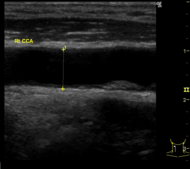

頸動脈エコー検査

頸動脈エコー検査(エコー検査は省略可です)